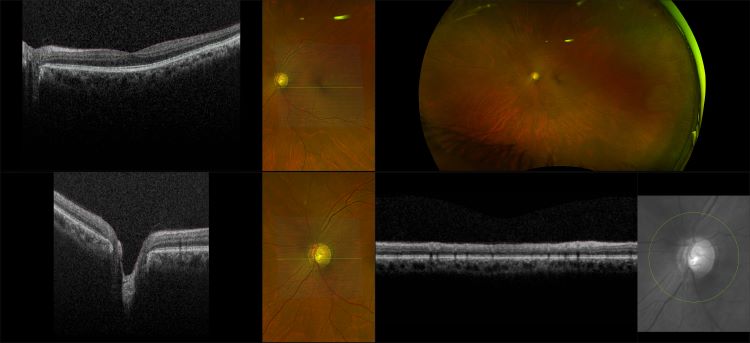

Monaco - Advanced Glaucoma, RG, OCT